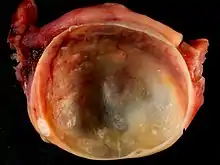

A simple ovarian cyst of most likely follicular origin

An ovarian cyst is a fluid-filled sac within the ovary.[1] Often they cause no symptoms.[1] Occasionally they may produce bloating, lower abdominal pain, or lower back pain.[1] The majority of cysts are harmless.[1] If the cyst either breaks open or causes twisting of the ovary, it may cause severe pain.[1] This may result in vomiting or feeling faint,[1] and even cause head aches.